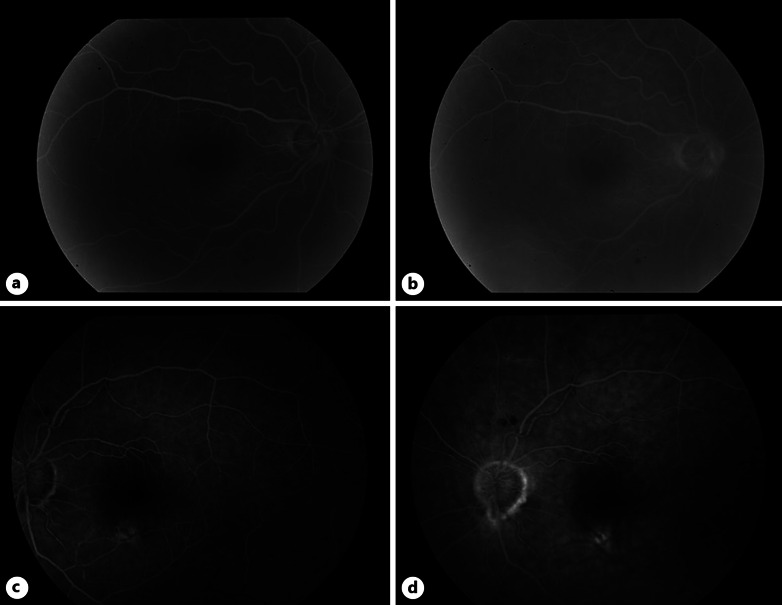

Introduction: Bilateral hemorrhagic hypopyon, also known as candy cane hypopyon, is an extremely rare presentation which we report as a unique case in association with intraocular mantle cell lymphoma (MCL).

Case presentation: A 63-year-old white male presented with a 3-week history of conjunctival injection OS that was unresponsive to erythromycin ointment and topical steroids, in the setting of recently discovered diffuse lymphadenopathy and malaise. On presentation, he was found to have bilateral hemorrhagic hypopyon. Lymph node biopsy was diagnostic of MCL, and subsequent anterior chamber paracentesis confirmed intraocular MCL. The patient was put into remission with intravitreal rituximab injections, systemic chemotherapy, and external beam radiation.

Conclusion: Cases of MCL with ocular involvement typically involve ocular adnexal structures, and seldom involve the uvea. Furthermore, this patient represents an extremely unusual case in his presentation with a hemorrhagic hypopyon.